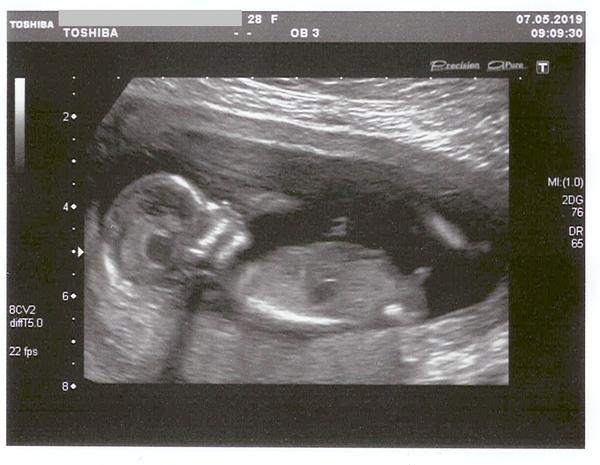

@pellullinka určitě holka, u nás si dr nebyl jistý ale mě bylo podle fotek jasné že to bude spíš holčička a v 15tt ni to potvrdil a teď na 3.screeningu nám ji krásně ukázala 😄

@pellullinka za mě taky jednoznačná holčička 🙂

@pellullinka Vypadá to na holčičku

@pellullinka podle mne holčička 😊